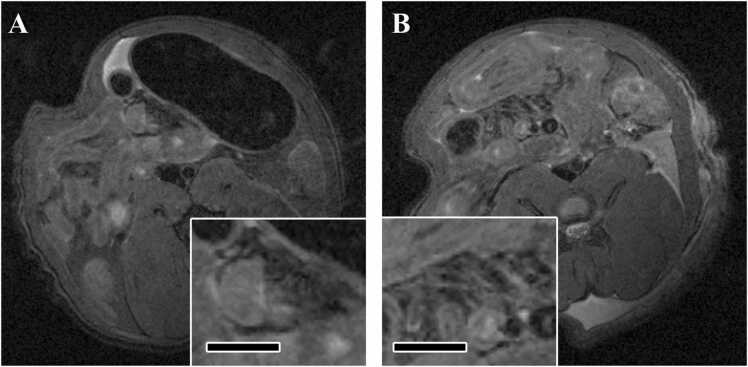

In the euthanized animals, some mesenteric arteries with low signal intensity were observed in the vehicle control group. On the other hand, in the FM-administered group, arteries were clearly visualized and the signal intensity around the artery was higher than that in the control group (Fig. 3).

Fig. 3.

Typical images of MRI of mesenteric arteries in euthanized animals in Experiment 2 (MRI after euthanasia and histopathology). (A) Axial image of MRI of the mesenteric artery in the vehicle control group. Inserts show higher magnification of the mesenteric artery. Bar in insert, 3 mm. (B) Axial image of MRI of the mesenteric artery in the FM group. Inserts show higher magnification of the mesenteric artery. Bar in insert, 3 mm. In the FM group, arteries were clearly visualized and the signal intensity around the artery was higher than that in the control group. Arteries are indicated by arrows.